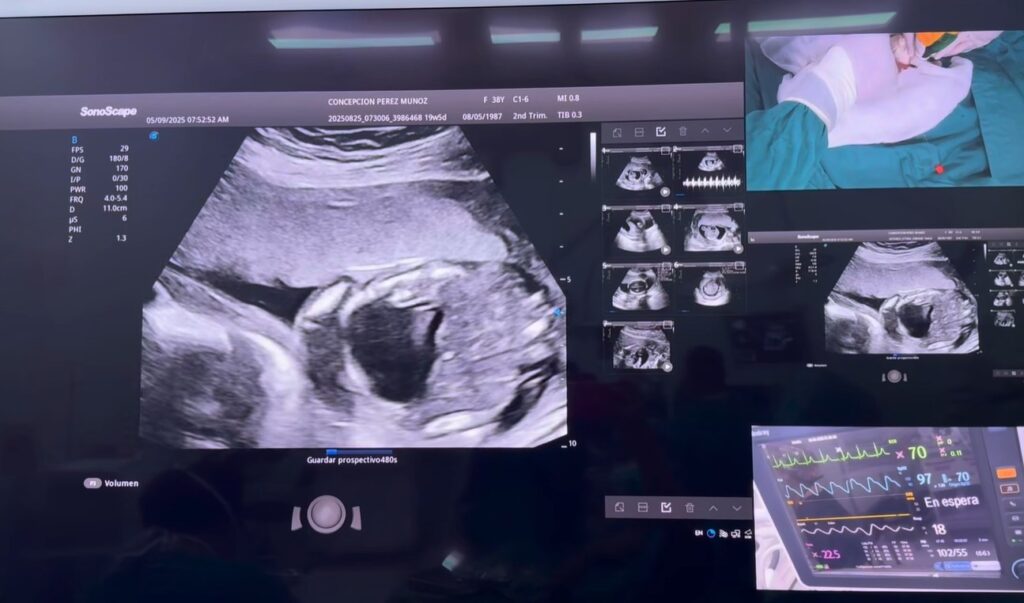

La intervención fue en un pacientito con hidrotórax fetal, a quien los doctores le extrajeron el líquido acumulado en los pulmones para favorecer su desarrollo.

Desde marzo del 2021, la cirugía fetal se realiza en el Hospital Bertha Calderón Roque, donde sin ningún costo, un equipo de especialistas a cargo del doctor Néstor Pavón, ofrecen este procedimiento para corregir anomalías en el vientre materno, ubicando a Nicaragua como pionero a nivel de la región.

La cirugía fetal, es una operación que se realiza dentro del útero materno para corregir malformaciones congénitas que podrían ser mortales o causar secuelas severas después del nacimiento.